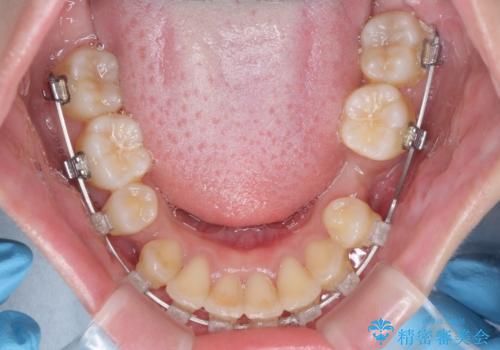

- クリアブラケット

- 1年10ヶ月

- 10-30回